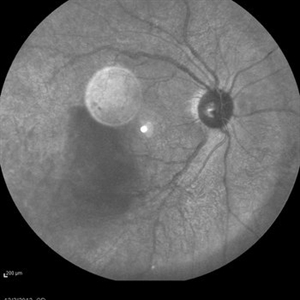

---thumb.jpg/image-square;max$300,300.ImageHandler) Pigmented Demarcation Line and A  Blood - containing Retinal Macrocyst Pigmented Demarcation Line and A  Blood - containing Retinal MacrocystNov 14 2013 by Hamid Ahmadieh, MD Color fundus photograph of the right eye of a 40-year-old man with longstanding retinal detachment showing a broad pigmented demarcation line and a retinal macrocyst . Notice blood inside the retinal macrocyst. Photographer: Elham Salehi , Negah Eye Center, Tehran Condition/keywords: demarcation line, fundus photograph, retinal macrocyst